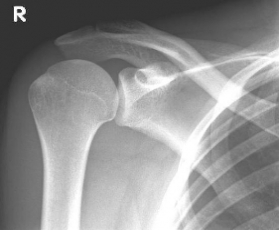

left: X-ray image of an omarthrosis

right: X-ray of a healthy shoulder joint

X-rays can be used to reliably diagnose the extent of joint wear. In the case of severe osteoarthritis, for example, the joint space and the formation of jagged edges (osteophytes) can be detected. If additional damage to the tendons of the shoulder (rotator cuff) is suspected, ultrasound examination (sonography) or magnetic resonance imaging (MRI) can help clarify the situation.